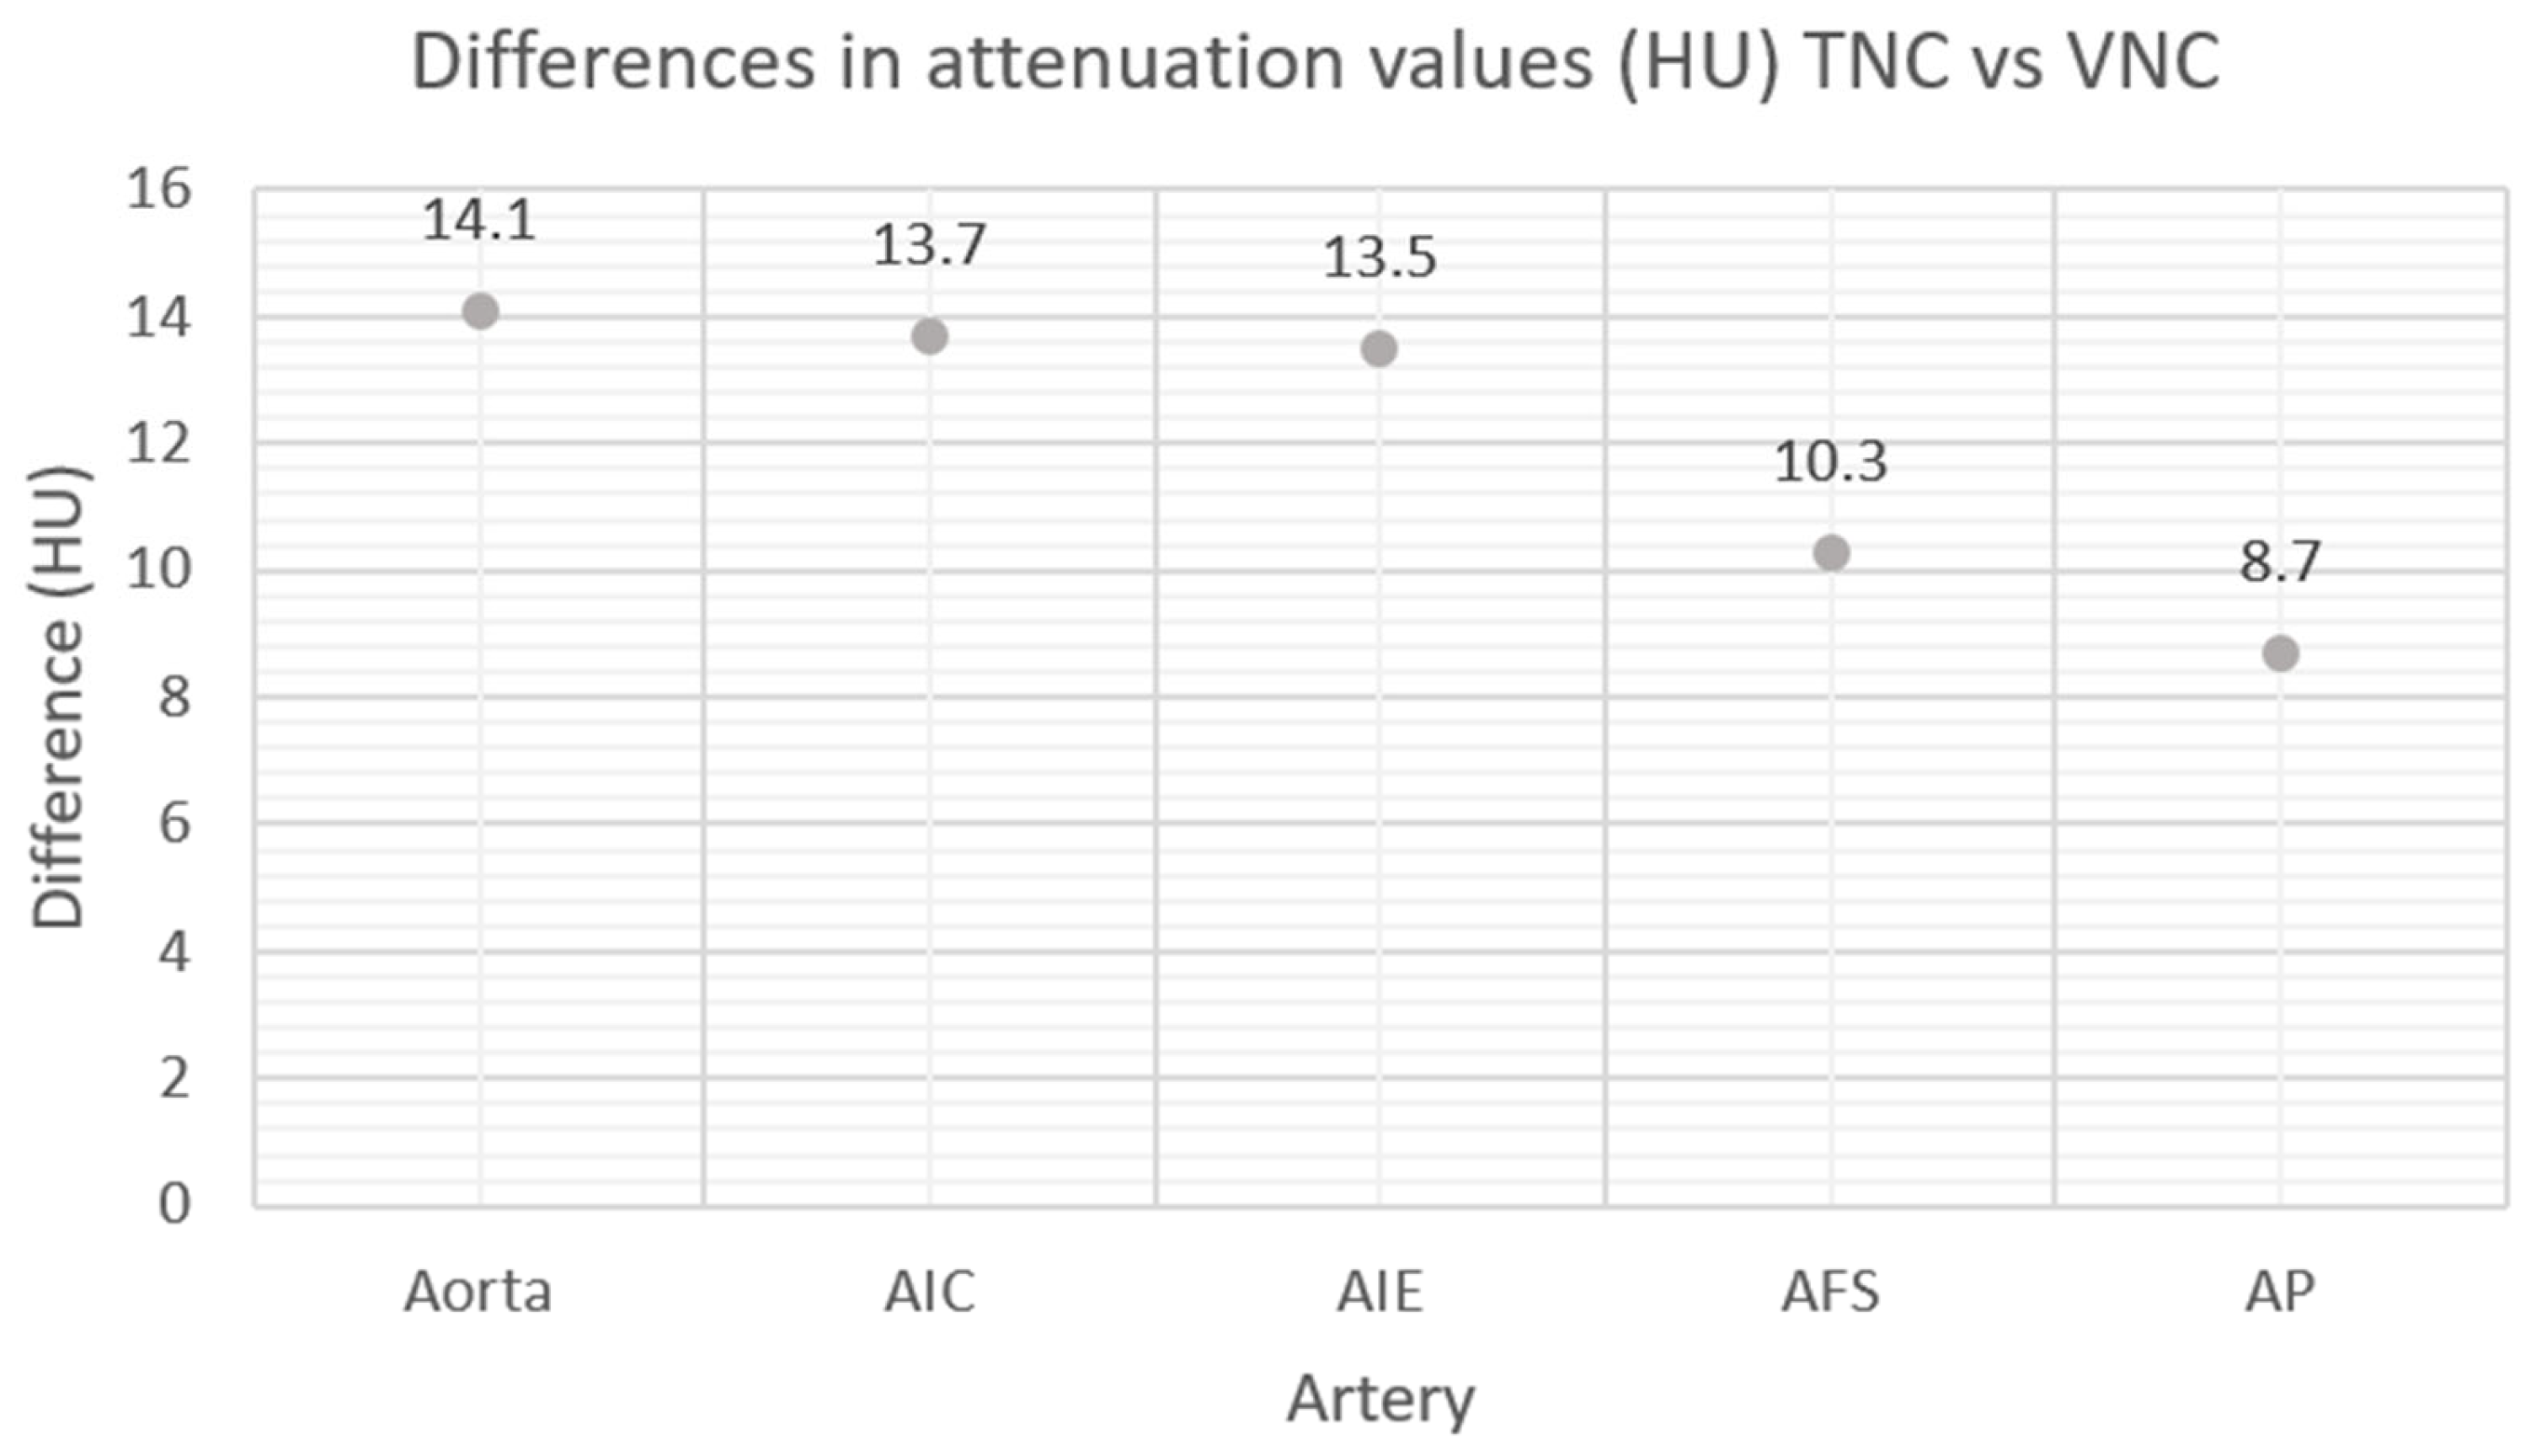

3. Results

| Anatomical Region | Contrast Phase | Mean Attenuation (HU) | Standard Deviation (DS) | p |

|---|---|---|---|---|

| Aorta | TNC | 47.1 | 6.6 | <0.000 |

| VNC | 33.0 | 8.2 | ||

| AIC | TNC | 47.8 | 8.9 | <0.000 |

| VNC | 34.1 | 11.4 | ||

| AIE | TNC | 46.6 | 9.4 | <0.27 |

| VNC | 33.1 | 6.4 | ||

| AFS | TNC | 48.5 | 9.0 | <0.001 |

| VNC | 38.2 | 10.4 | ||

| AP | TNC | 49.4 | 7.8 | <0.000 |

| VNC | 40.7 | 9.6 |